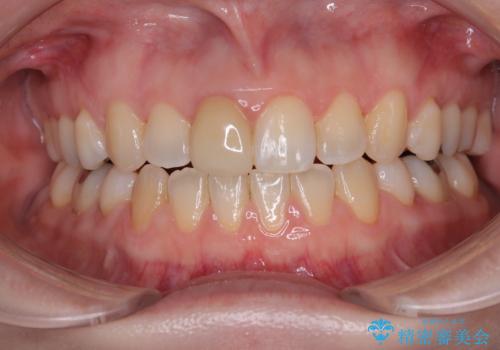

ワイヤー矯正後の後戻り 出っ歯を治したい マウスピース矯正

インビザライン・モデレートを用いて気になる後戻りを矯正治療